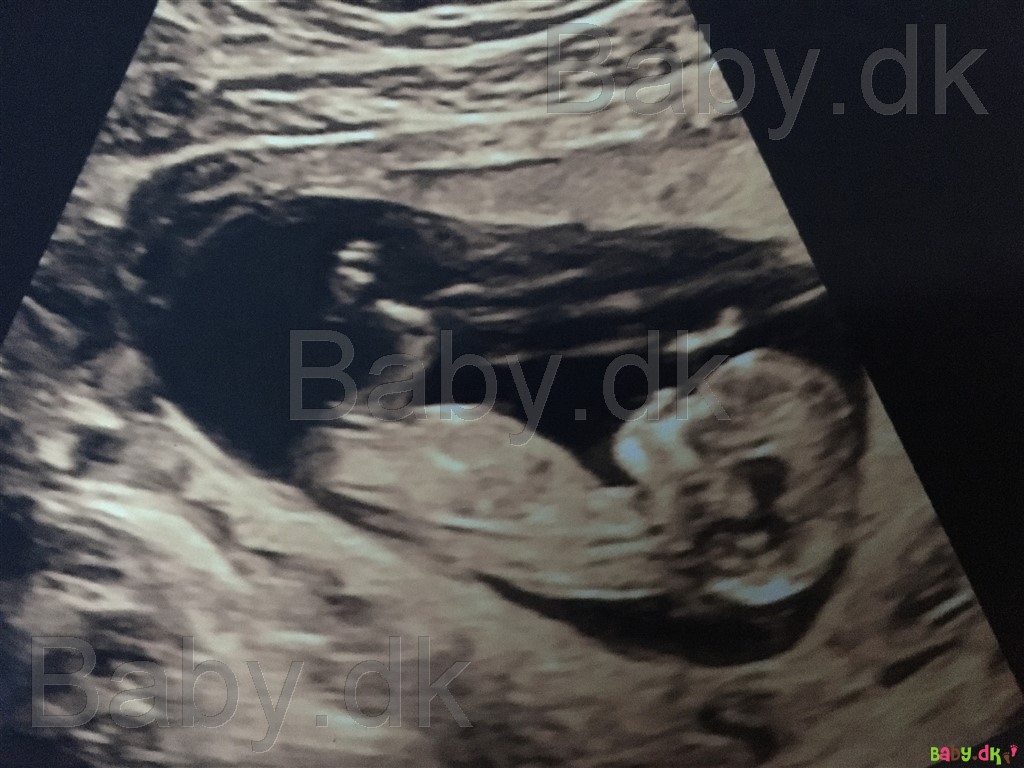

Vi har lige været til nakkefoldsscanning idag, hvor alt så godt ud. Men jeg er både spændt og utålmodig på kønsscanningen om 2 uger og tænkte der sikkert var nogle garvede der ville komme med et bud på om det er en dreng eller pige vi venter os?

Vi har selv haft fornemmelsen af at det var en pige, men jeg er kommet i tvivl og synes at kunne ane noget på billedet?

Jeg er 12+4. Håber nogle vil give et bud, ønsker alle en god dag